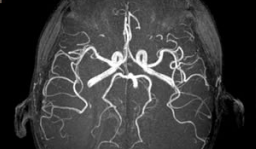

Aparatos de radiodiagnóstico:

• Radiografía de rayos x

• TAC: Tomografía axial computarizada escáner

• RMN: Resnancia magnética nuclear

• PET: tomografía por emisión de positrones